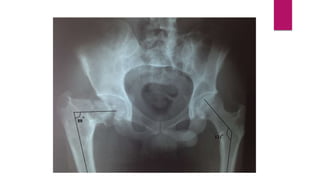

 Protrusio acetabuli and proximal femoral shepherd’s crook deformity

 Combination of protrusion, fracture and abnormal hip mechanics frequently

results in osteoarthritis, requiring total joint replacement.